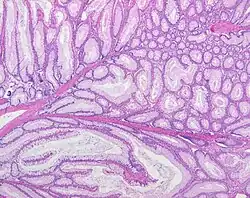

Histopatologiczny obraz polipów hamartomatycznych w PJS jest inny niż wszystkich pozostałych polipów jelita grubego, co przypuszczalnie wiąże się z odmiennym przebiegiem sekwencji patogenezy tych zmian. W polipach typu Peutza-Jeghersa obserwuje się wydłużone, palisadowato ułożone komórki nabłonka i torbielowate poszerzenia gruczołów jelitowych, nakładające się na drzewkowatą sieć włókien mięśniówki gładkiej. Wyraźne są niekiedy przepełnione śluzem komórki kubkowe i (bardzo charakterystyczna) pseudoinwazja histologicznie łagodnych komórek nabłonka poza błonę podstawną, w rzeczywistości będąca wyrazem błędnej organizacji warstw nabłonka (epithelial misplacement)[11][12]. Nie obserwuje się atypii komórek ani niskiego zróżnicowania, typowych dla gruczolaków, tak samo nie wykazuje się cech cytogenetycznych dysplastycznych gruczolaków w polipach PJS. Polipy hamartomatyczne w zespole polipowatości młodzieńczej (JPS, [OMIM#174900]) powstają w niewyjaśnionym mechanizmie jako skutek mutacji germinalnej genu SMAD4/DPC4, ale histologicznie są odmienne niż w PJS, a ryzyko nowotworzenia w tych dwóch zespołach też nie jest takie samo.